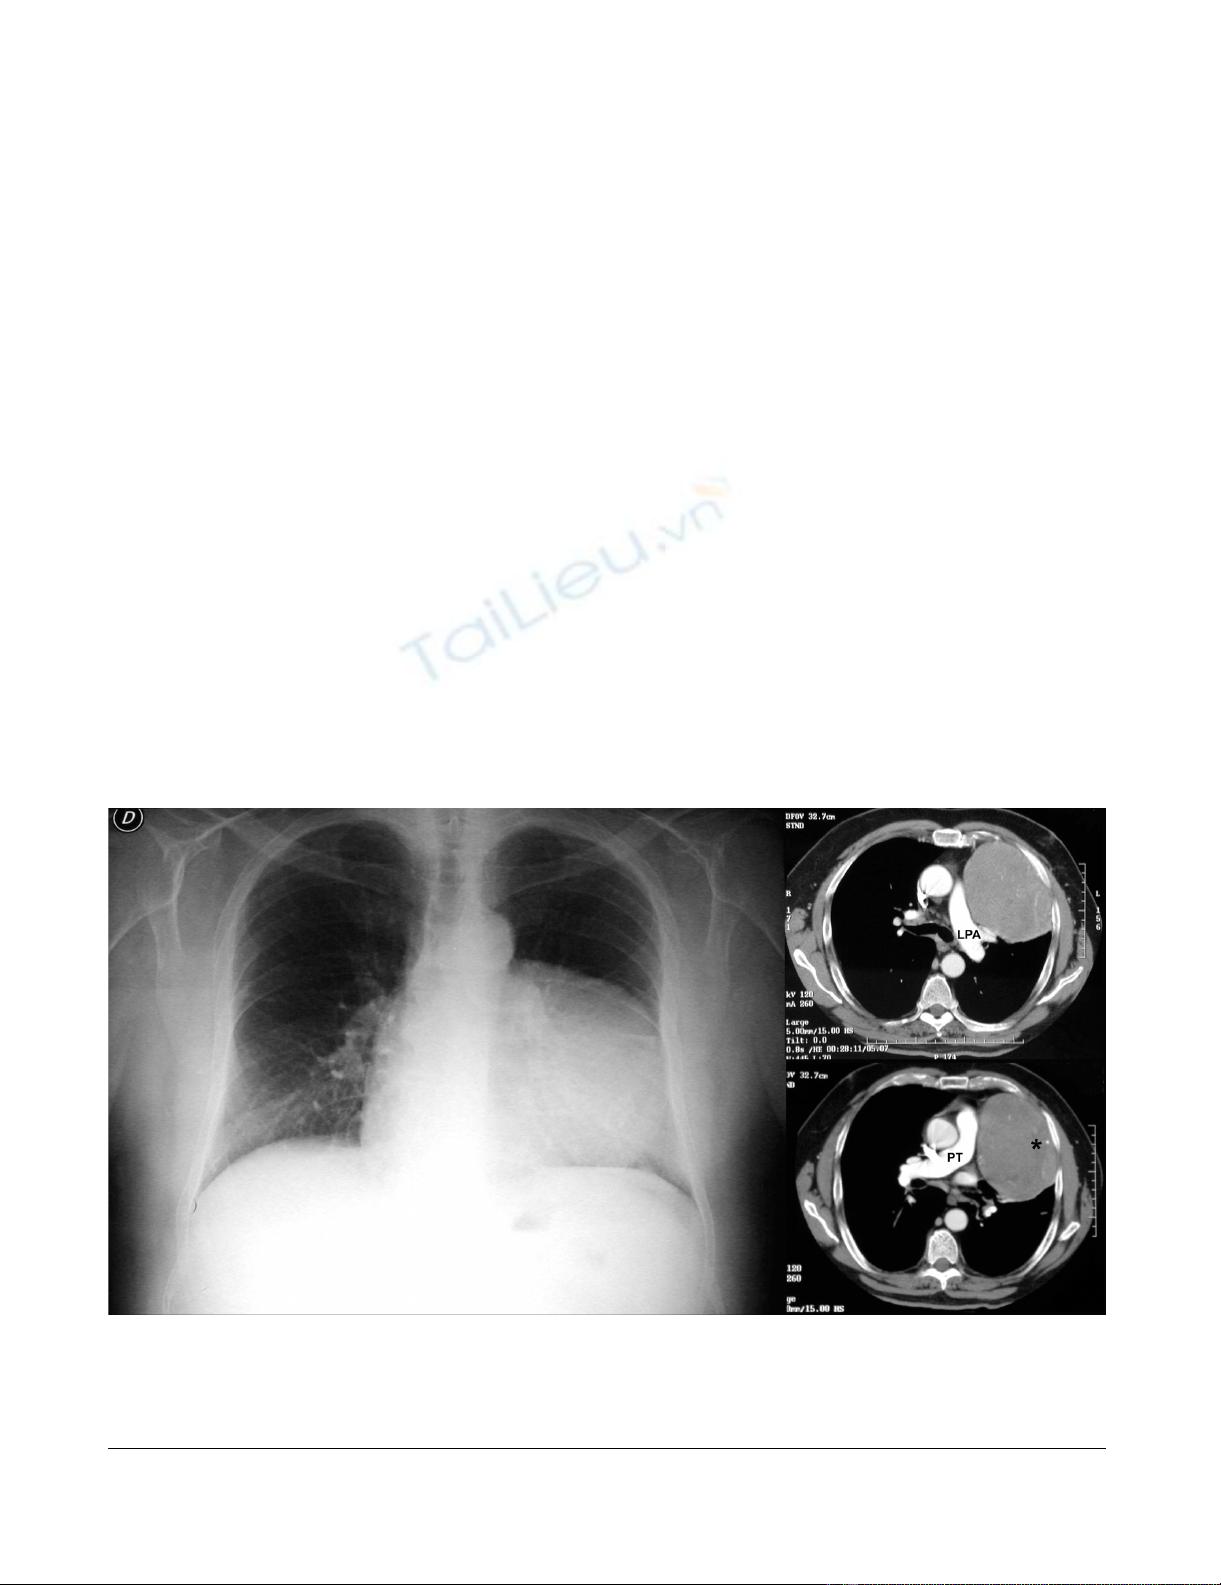

Left panel: chest x-ray showing a large opacity on the left sideFigure 1

Left panel: chest x-ray showing a large opacity on the left side. Right panel: the CT scan of the chest showing a solid mass of 11

× 8 cm in the left hemi thorax, with vertical extension of 10 cm, mild enhancement after contrast medium infusion and some

calcifications in the basal part (asterisk). The lesion is in close relation with chest wall, left pulmonary artery (LPA) and pulmo-

nary trunk (PT), without signs of local infiltration.